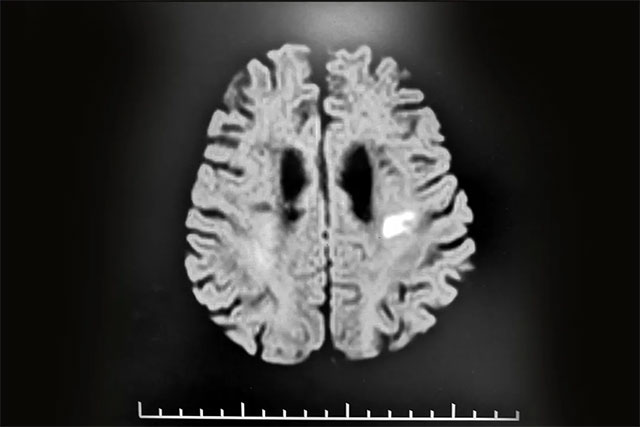

张静波主任还接诊了这样一位脑梗患者:今年7月初,68岁的程先生(化名),第一次患脑血管疾病,并以脑梗死形式发病,根据其头部CT影像结果所示,其脑梗病灶并不是很大,但患者入院不久后就出现了一些精神障碍,表现为痴呆、答非所问,自言自语,记忆力减退,有时骂人,甚至有暴力的行为,这让家人不知所措。

▲ 患者头部CT所示:其脑梗病灶并不严重

对此,张静波主任解说,一般正常情况,只有当患者一次出现大面积脑梗,或其脑组织损害一次性超过80ml以上,才可能出现痴呆等表现。但患者程先生其脑梗病灶面积实际并不是很大,这就无法解释他出现痴呆、骂人及记忆力减退等精神症状。